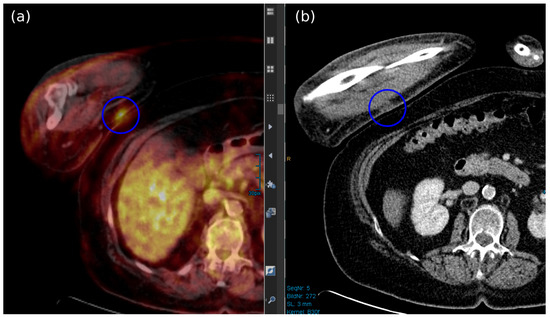

- Akaike, G.; Akaike, T.; Fadl, S.A.; Lachance, K.; Nghiem, P.; Behnia, F. Imaging of merkel cell carcinoma: What imaging experts should know. Radiographics 2019, 39, 2069–2084. [Google Scholar] [CrossRef]

- Oh, H.Y.; Kim, D.; Choi, Y.S.; Kim, E.K.; Kim, T.E. Merkel Cell Carcinoma of the Trunk: Two Case Reports and Imaging Review. J. Korean Soc. Radiol. 2023, 84, 1134–1139. [Google Scholar] [CrossRef]